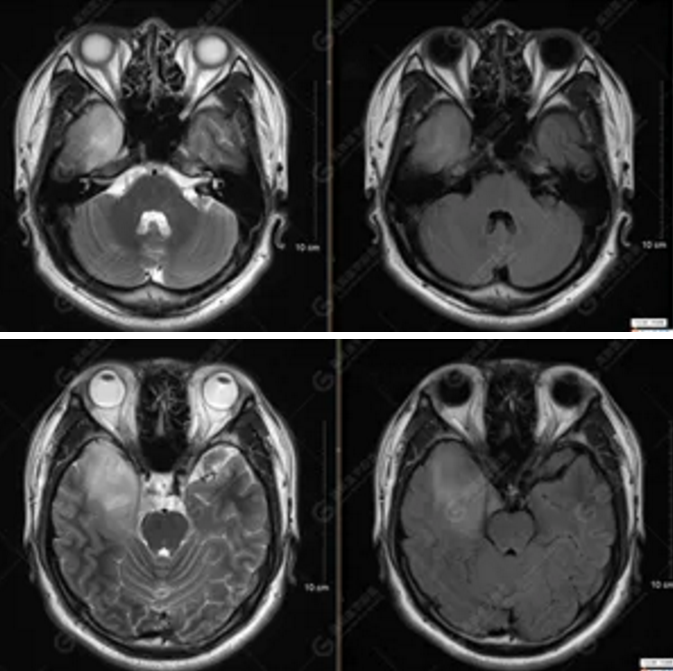

【MRI平掃及增強(qiáng)檢查所見(jiàn)】右側(cè)額顳島葉、右側(cè)海馬及右側(cè)基底節(jié)區(qū)見(jiàn)一團(tuán)塊狀異常信號(hào)影,累及右側(cè)下丘腦及視交叉,大小約5.1cm×4.5cm×4.3cm,呈長(zhǎng)T1長(zhǎng)T2信號(hào),F(xiàn)LAIR序列呈等、稍高信號(hào),DWI序列呈稍高信號(hào),ADC圖高信號(hào),增強(qiáng)后無(wú)明顯強(qiáng)化;病灶周?chē)?jiàn)片狀長(zhǎng)T1長(zhǎng)T2水腫信號(hào)影,F(xiàn)LAIR序列呈高信號(hào),病灶內(nèi)見(jiàn)右側(cè)大腦中動(dòng)脈穿行。余腦實(shí)質(zhì)內(nèi)未見(jiàn)局灶性信號(hào)異常,增強(qiáng)后未見(jiàn)異常強(qiáng)化。右側(cè)側(cè)腦室輕度受壓,余腦室、腦池大小、形態(tài)均正常,中線(xiàn)結(jié)構(gòu)居中